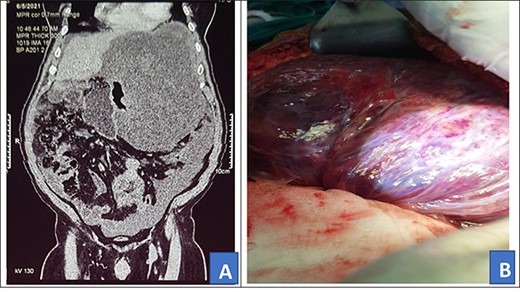

On examination, he was fair, with a temperature of 36.4°C, a pulse rate of 72 beats per minute and had a blood pressure of 128/85 mmHg. The abdomen was grossly distended with a palpable mass in the left upper quadrant. He had no hepatomegaly, He had normal bowel sounds. Other systems’ exam was grossly normal. An abdominal CT was done and it showed a 25.8 × 19.6 × 15.3 cm mass in the left upper abdominal quadrant (Fig. 2A). The patient was scheduled for an exploratory laparotomy.

Preoperative abdominal CT scan (A) and intra-operative picture (B) for Patient 2.

Intra-operatively, a giant 28 × 30 cm retro gastric mucinous tumor was found involving the greater curvature of the stomach, the spleen and part of the left hemi diaphragm (Fig. 2B). The patient was also found to have moderate ascites of 500 ml. The tumor was mobilized and resected. In addition, the greater curvature of the stomach, part of the left hemi diaphragm and spleen were resected. Diaphragm was repaired with ethylon 1–0.